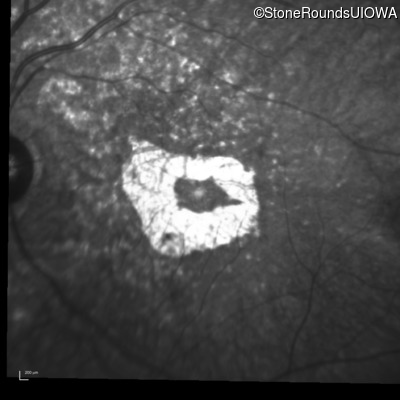

Blue Autofluorescence - Right - 20/20 -2

Exemplar